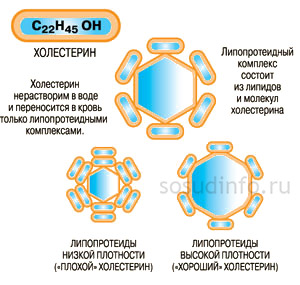

Липопротеины высокой и низкой плотности играют ключевую роль в обмене холестерина и здоровье сердечно-сосудистой системы. Врачи отмечают, что ЛПВП (липопротеины высокой плотности) часто называют “хорошим” холестерином, так как они помогают удалять избыточный холестерин из организма, снижая риск атеросклероза. Нормальные уровни ЛПВП варьируются, но обычно составляют более 1,0 ммоль/л для мужчин и более 1,3 ммоль/л для женщин. В то же время ЛПНП (липопротеины низкой плотности) считаются “плохими”, поскольку их повышенные уровни могут привести к образованию бляшек в сосудах. Нормальные значения ЛПНП не должны превышать 3,0 ммоль/л. Врачи предупреждают, что повышение уровня ЛПНП может быть связано с неправильным питанием, малоподвижным образом жизни и генетической предрасположенностью. Регулярные проверки уровня липопротеинов в крови и соблюдение здорового образа жизни могут помочь поддерживать баланс и снизить риск сердечно-сосудистых заболеваний.

Липопротеины высокой плотности (ЛПВП) и низкой плотности (ЛПНП) играют ключевую роль в обмене холестерина и здоровье сердечно-сосудистой системы. ЛПВП часто называют “хорошим” холестерином, так как они помогают выводить излишки холестерина из клеток и сосудов, снижая риск атеросклероза. Нормальные уровни ЛПВП варьируются, но обычно считаются оптимальными значения выше 1,0 ммоль/л для мужчин и 1,3 ммоль/л для женщин. В то же время, ЛПНП, или “плохой” холестерин, способствует накоплению холестерина в артериях, что может привести к сердечно-сосудистым заболеваниям. Нормальные уровни ЛПНП должны быть ниже 3,0 ммоль/л. Повышение ЛПНП часто связано с неправильным питанием, малоподвижным образом жизни и генетическими факторами. Люди настоятельно рекомендуют следить за уровнями этих липопротеинов, так как их баланс является важным показателем здоровья.